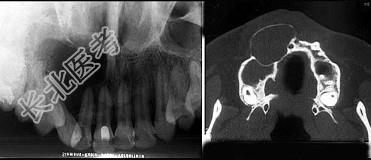

单项选择题位于上颌侧切牙与尖牙之间的非牙源性囊肿(影像检查如图)是 ( )

A、球上颌囊肿

B、鼻腭囊肿

C、正中囊肿

D、鼻唇囊肿

E、角化囊肿